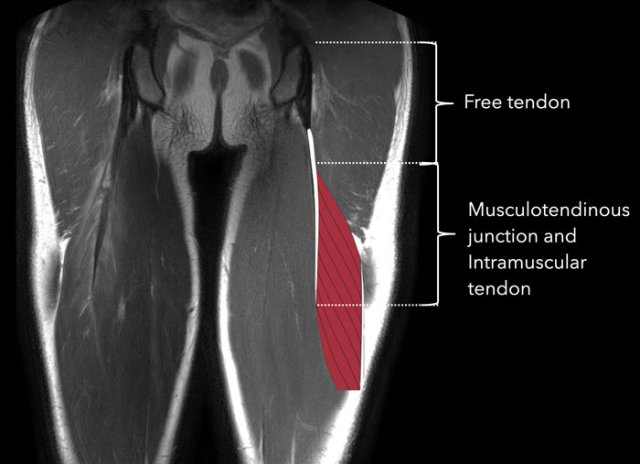

Here the anatomy is shown on a coronal MR image.

The insertion of the semitendinosus (2) on the hamstring origin is partly muscular.

The free tendon is attached to the ischial tuberosity, it has no muscle fibers attached to it.

The interface between tendon and muscle fibers is the musculotendinous junction.

The part of the tendon with muscle fibers attached to it is the intramuscular tendon.

The muscle itself is surrounded by the fascia.